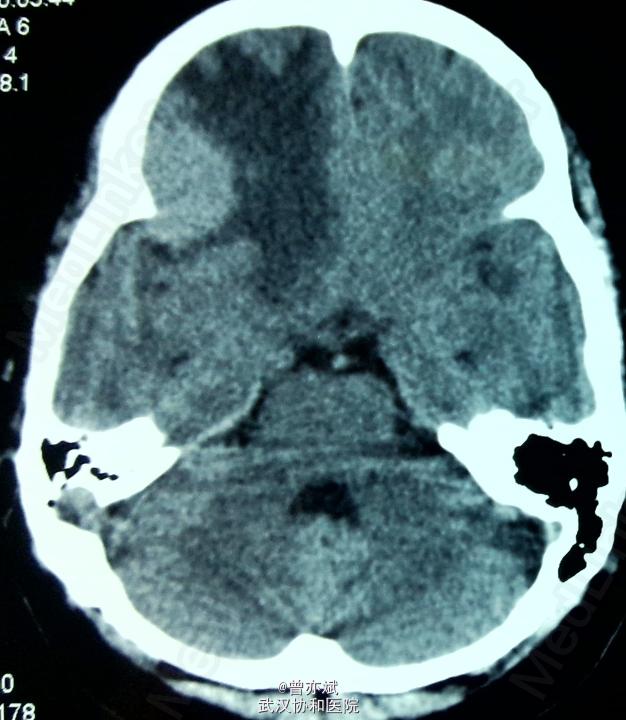

诊断:脑膜瘤 处理:手术切除。 病理报告为脑膜瘤。

术后CT如下